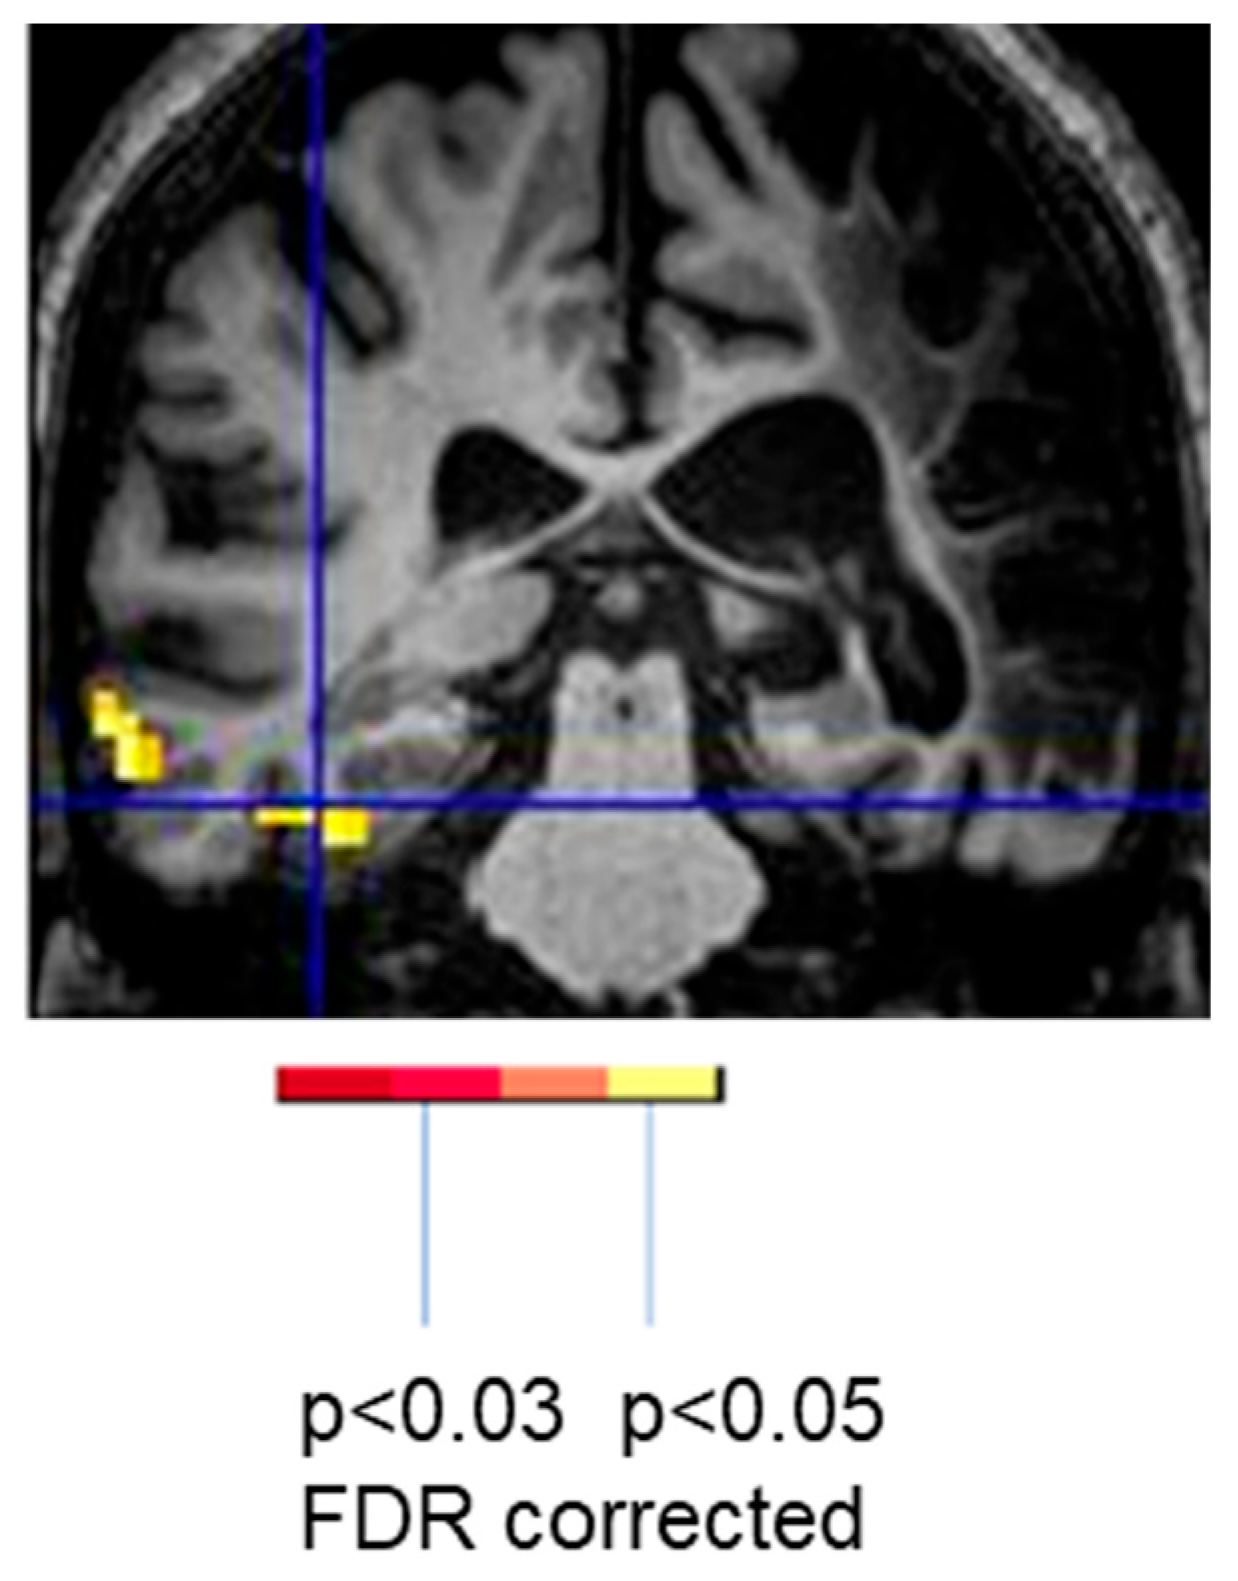

To illustrate the effect of language task, the woman described earlier who showed only left occipital activation with spelling showed bilateral activation and more left perilesional activation during reading (silent reading of words versus viewing of scrambled letter strings) (Figure 4). She read the words with 100% accuracy outside of the scanner that day. Her activation with reading was essentially the normal pattern seen in neurotypical controls [30]. While it might be tempting to conclude that the minimal activation of perilesional tissue during spelling was due to diaschisis, there was no evidence of diaschisis during the reading task the same day [26,29].

Figure 4.

Task-related fMRI activation at Day 3 (acutely) post-stroke in the same woman associated with spelling (80% correct; left) and reading (100% correct; right).